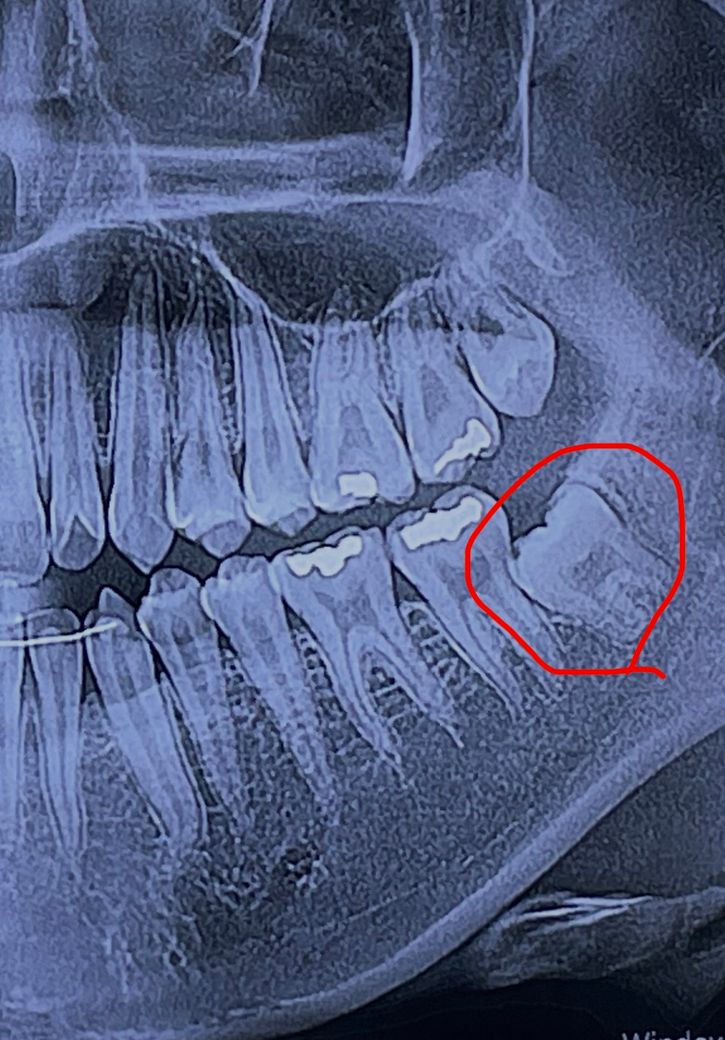

완전 매복 하악 사랑니 발치 난이도가 궁금합니다

1. 왼쪽 하악 사랑니가 완전 매복인데 그냥 두어도 될까요? 아니면 발치가 꼭 필요해보이나요?

2. 제 케이스의 경우 왼쪽 하악 사랑니 발치 난이도가 높을까요?

• 1번 째 사진

발치자체 난이도는 높지 않지만 매복 깊이가 상당히 깊어서 잇몸뼈 삭제를 많이 해야될것같습니다.

1. 옆 어금니와 인접하여 있으므로 영향을 줄 수 있어 빼는 것이 좋을 것 같습니다.

2. 발치 난이도는 높아보입니다.